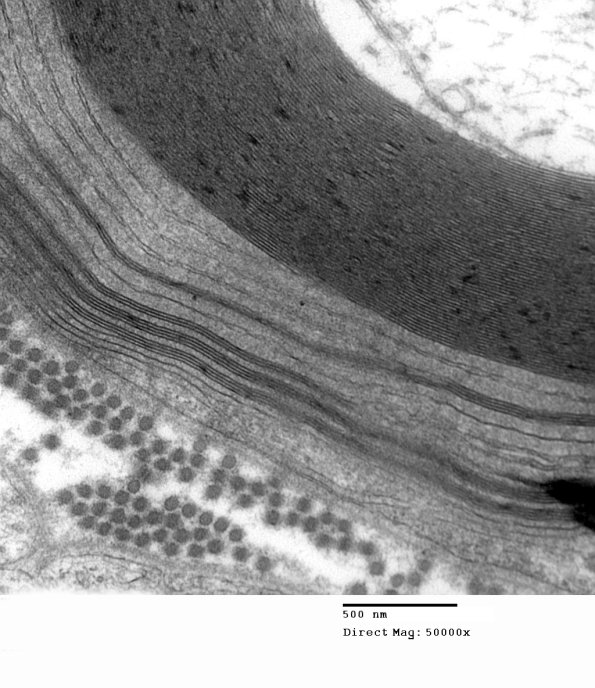

Particularly complex WSM involving multiple lamellae. (electron micrographs)